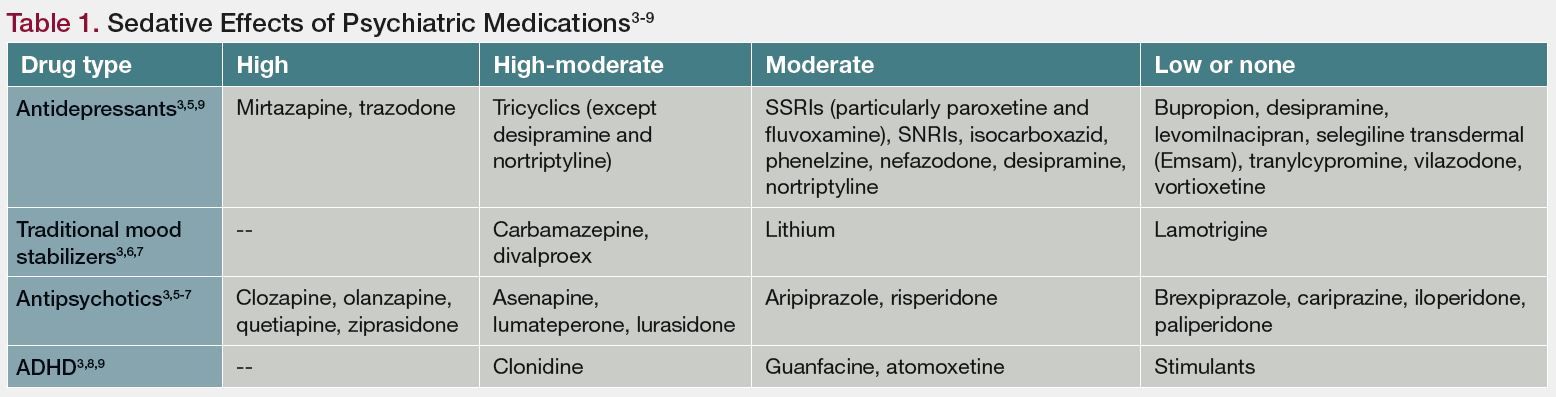

Sedation The Ups And Downs Of A Side Effect

Sedation The Ups And Downs Of A Side Effect

Sedation The Ups And Downs Of A Side Effect